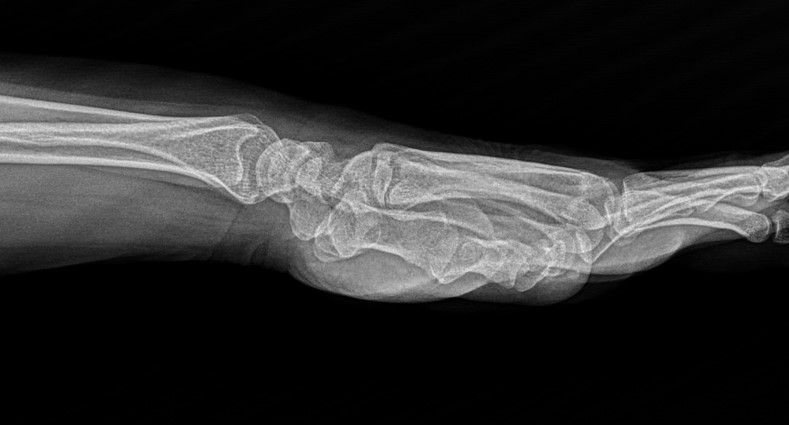

Case 13 - Scaphoid Fracture

17 yr, male, student, non smoker, right hand dominant

History of sports injury four months ago, he fell on his right hand, no hospital admision in the first place

First admitted another hospital 3 months ago, thumb spica splint applied

When he admitted to our clinic cast is removed